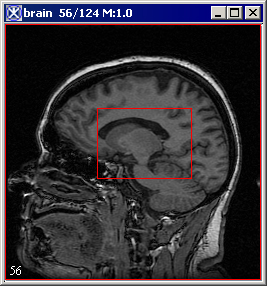

To create 3D rectangular VOIs

- Draw 3D Rectangular VOI

1 Click the 3D rectangular VOI icon.

2 Click the area on the image where you want a corner of the rectangle to appear.

3 Drag the pointer. As you drag the pointer, the rectangle changes in size.

4 Release the mouse button when the rectangle is the desired size.

Unlike 2D rectangular VOIs, 3D rectangular VOIs appear on all slices in the dataset.